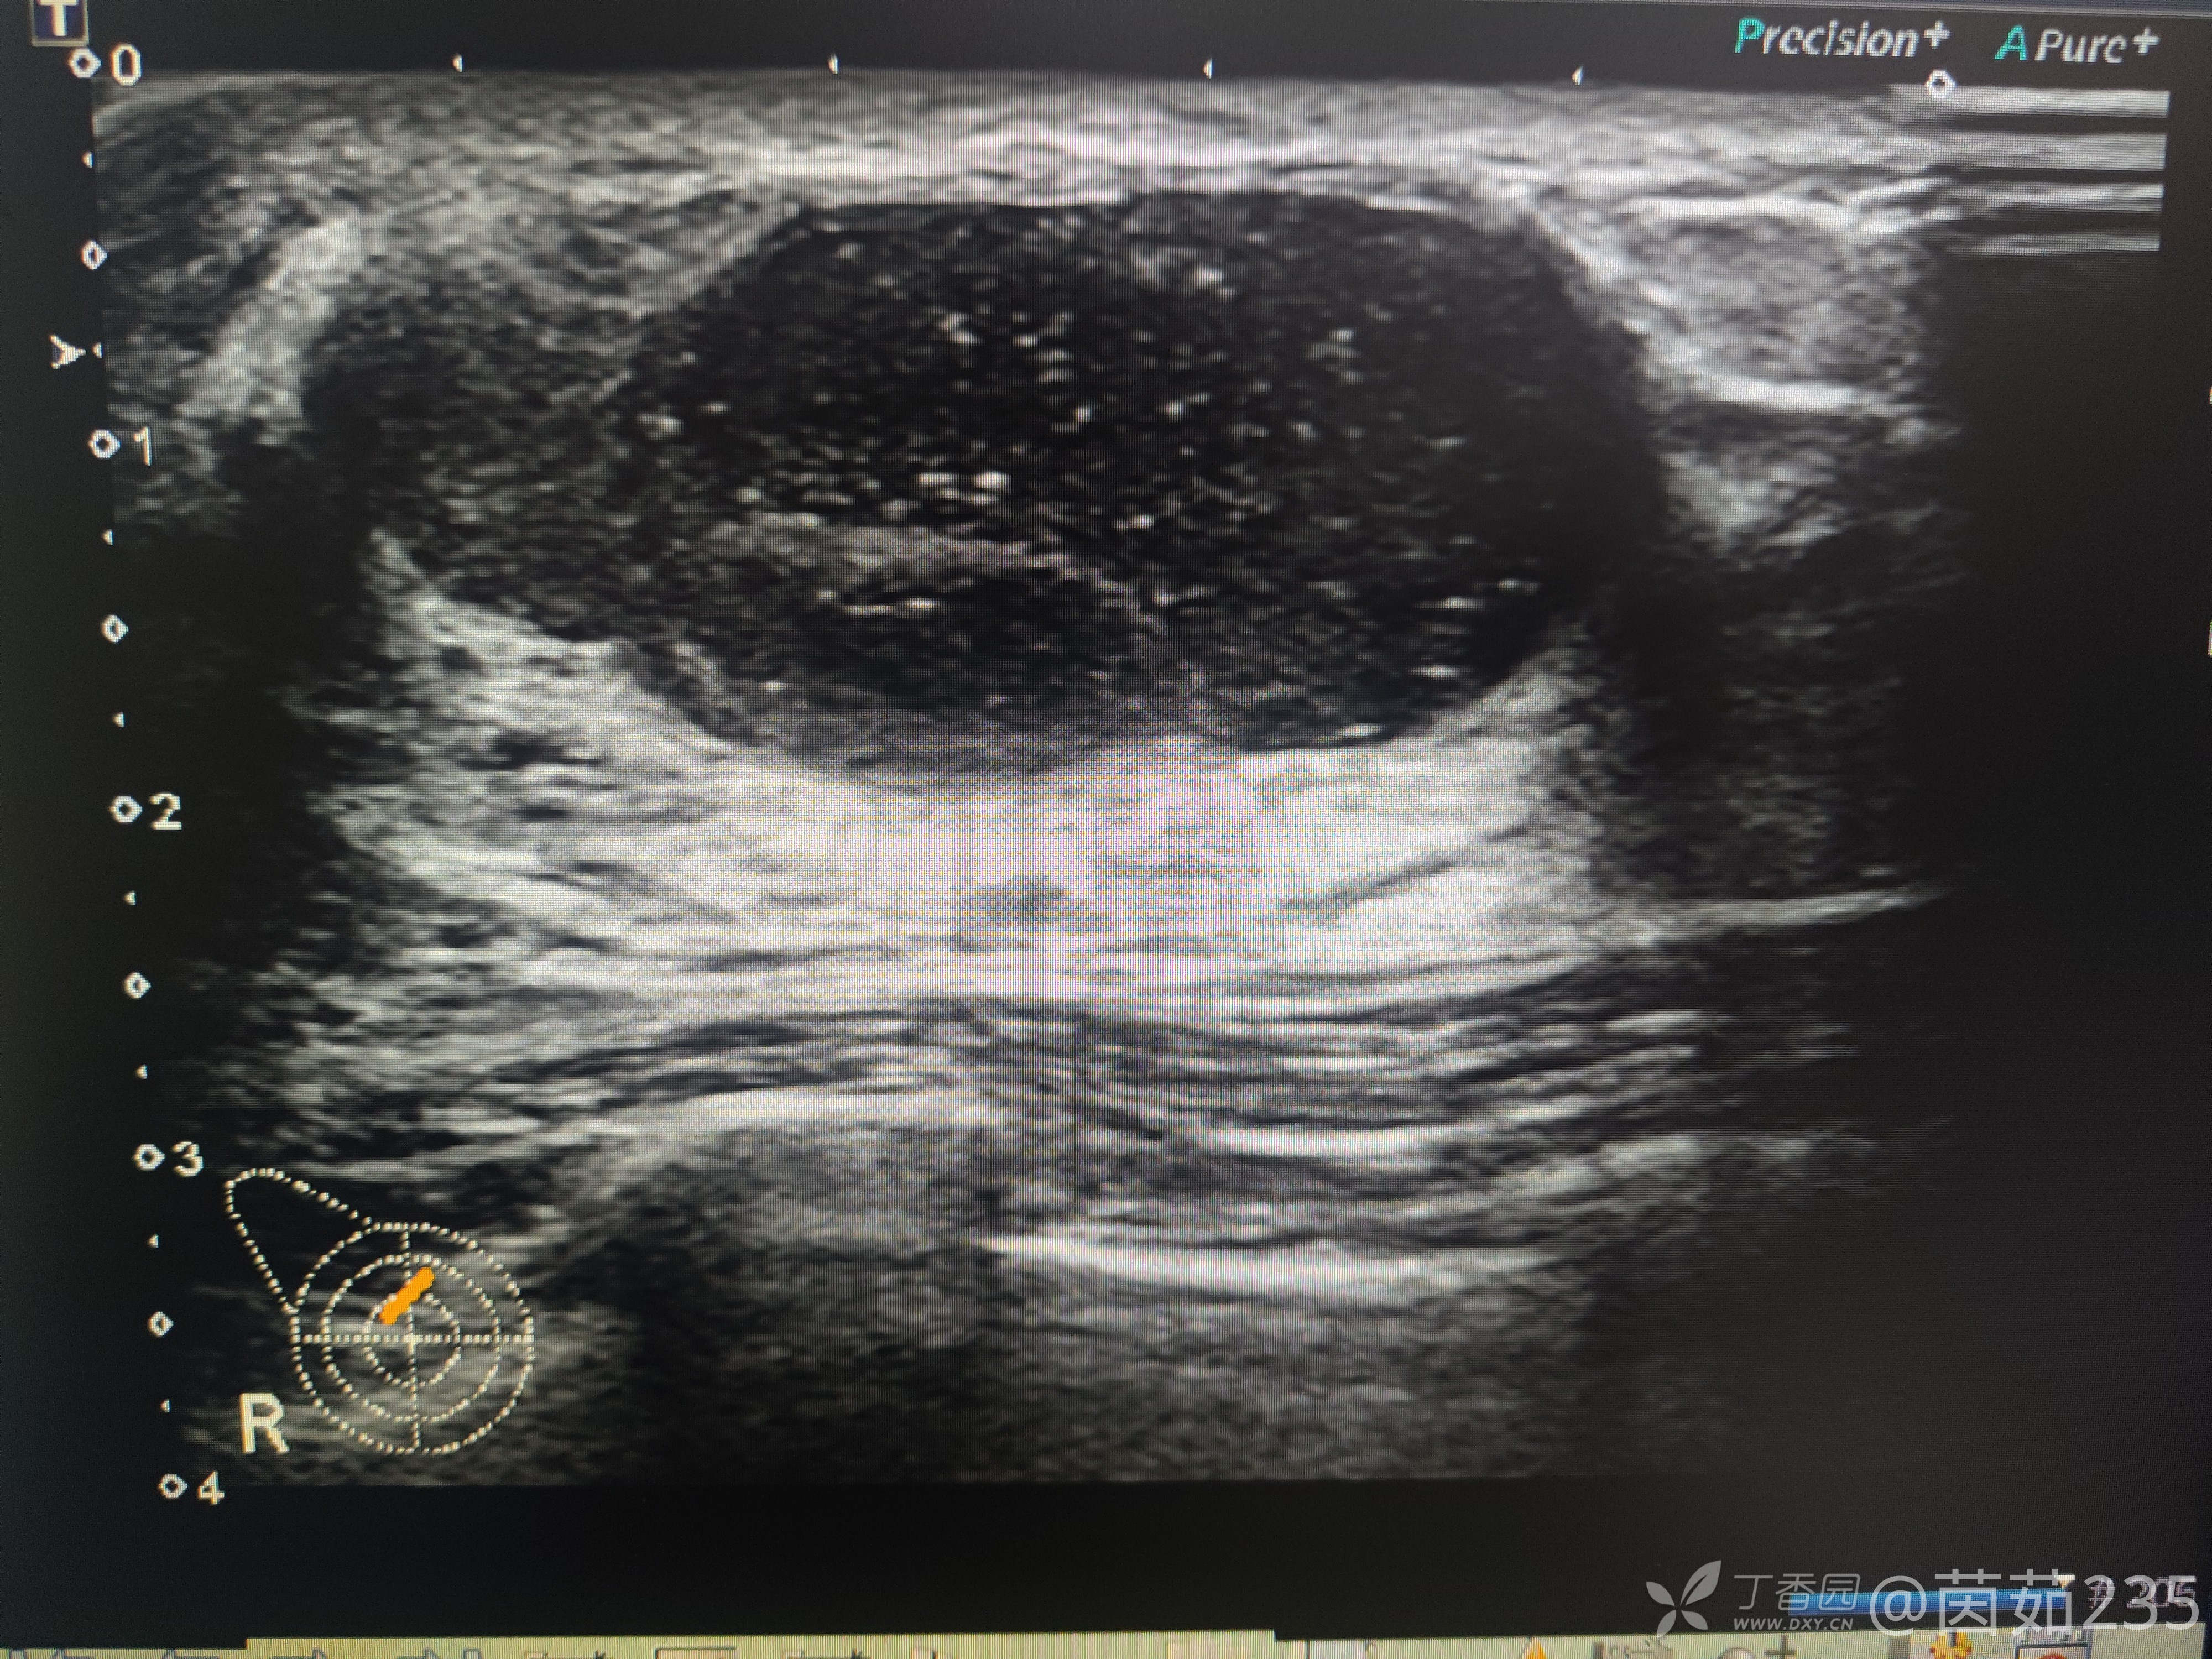

右侧乳腺12点乳晕后方腺体内可见一低回声包块,大小37✖️16mm,边界清,壁厚,内回声不均,可见数个彗星尾。来看看图,你们觉得该分几类?考虑是什么?